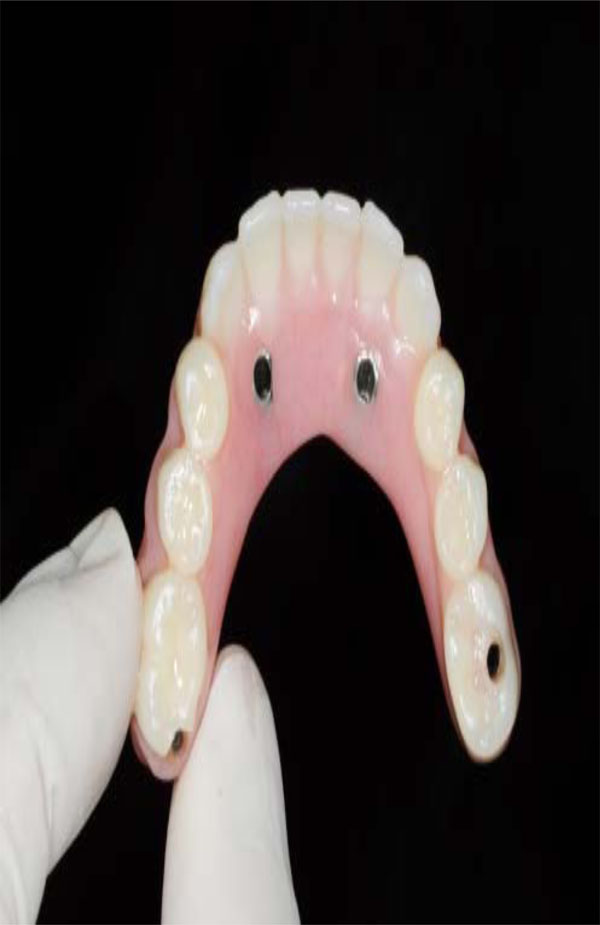

Intaglio surface of maxillary hybrid has been custom designed in order to improve esthetics and phonetics.

computer-aided manufacturing (CAD/CAM) technology for the design and subtractive rapid prototyping technology for the fabrication of the zirconia frameworks. Once the design of the framework is completed, the data is transferred to a milling unit for fabricating the framework. The frameworks can be fabricated from fully sintered zirconium oxide or partially sintered zirconium-oxide blanks. The proponents of partially sintered frameworks claim that micro cracks may be introduced to the framework during the milling procedure of a fully sintered blank, whereas the proponents of milling of a fully sintered blank claim that because no shrinkage is involved in the process the marginal fit is superior [59, 60]. Probably the partially sintered zirconium technique presents several appealing advantages; the fully customization of framework into monolithic shape (Fig. 13) and intrinsic colorization (Fig. 14). Such ability to control the framework contours and colors provides the ceramist and the clinician additional flexibility, while providing the patient with robust and esthetic restorations (Fig. 15).